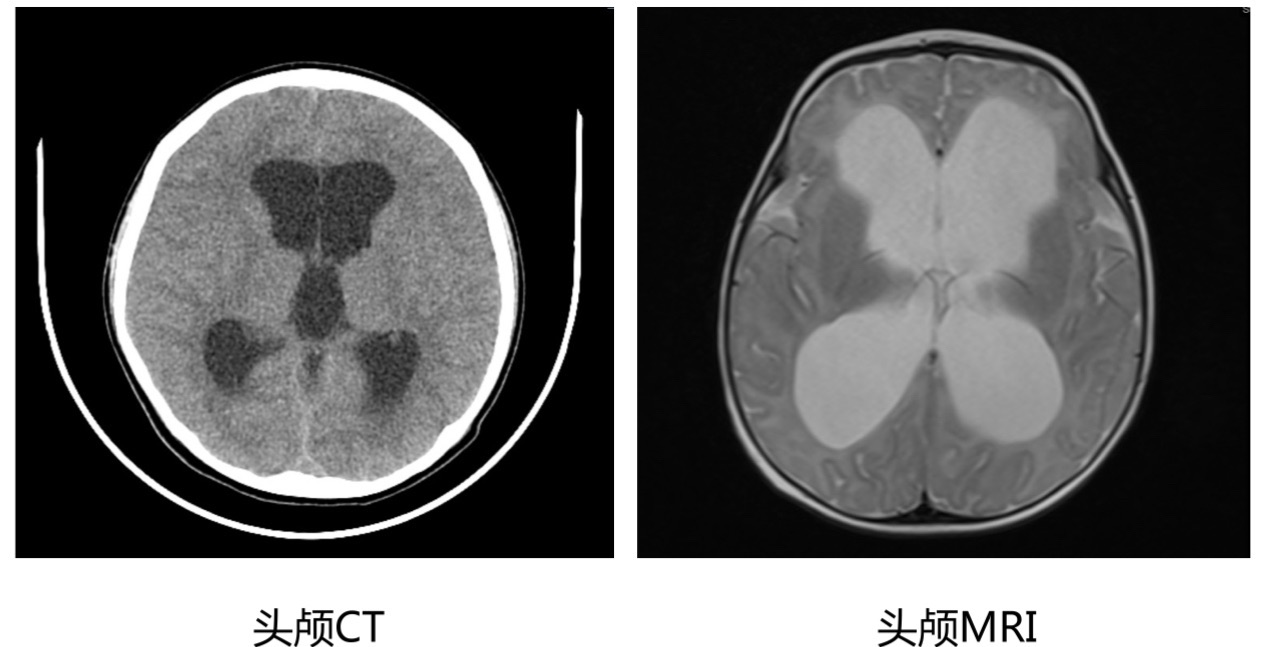

脑积水的宝宝会有哪些表现呢? 脑积水的表现主要取决于发病时间(相对于颅缝闭合的时间)、颅内压增高的速度及持续时间以及是否伴有相关的结构异常。 1. 婴儿和儿童轻度脑积水可能没有症状,通常是偶然检查发现的; 2. 颅缝闭合前的脑积水宝宝:最常见的表现就是头围增大,也就是前面提到的“大头娃娃”,头太大,颈部肌肉比较薄弱,以至于出现抬头不稳或者不能抬头,与同龄宝宝相比,有可能存在发育迟缓,比如说到了该抬头的月份不能抬头、不能翻身、不能坐起、不能站立等等,有些宝宝甚至还会出现发育倒退、行为改变,比如容易激惹等; 3. 年龄较大的儿童:因为颅缝闭合了,少了颅缝和囟门能够缓冲的空间,所以脑积水多的情况下,会出现明显的颅内压增高的表现,包括清晨头痛明显、恶心、呕吐、行走不稳、行为改变等等; 4. 急性脑积水:除了头痛、呕吐,还可能会出现意识状态的改变,包括昏睡、嗜睡等; 5. 外观上的异常:婴幼儿的脑积水比较容易从外观上发现,包括头围增大,头皮静脉很明显、曲张或者显露、囟门张力高、“落日征”(眼睛不能上视,总是下翻,露出眼白部分)等。 怀疑脑积水应该做哪些检查呢? 1. 定期监测头围:如果婴儿在孕期产检有脑室增宽、出生时有头围增大,连续监测头围的测量值总是在标准曲线以上,表明头部生长过度,应怀疑婴儿有脑积水,要做进一步的检查。 2. 颅腔B超:对于新生儿和小婴儿,即前囟还没有闭合的宝宝,可以选择做个颅腔B超,非常便捷,一般不需要镇静。 3. 头颅CT或者头颅MRI:对于疑似脑积水的年龄较大的婴儿和儿童,应该进行头颅CT或者头颅MRI检查,除了评估脑积水的程度,还可以发现结构异常或者肿瘤等后天因素。 4. 眼底检查评估视乳头水肿:脑积水引起颅压增高还会导致视乳头水肿、视物不清楚、视力下降等情况,对于脑积水的年龄较大的儿童,可以做眼底检查评估是否存在视乳头水肿,也可以侧面反应脑积水导致颅压增高的情况。

脑积水头颅CT和MRI的影像学表现